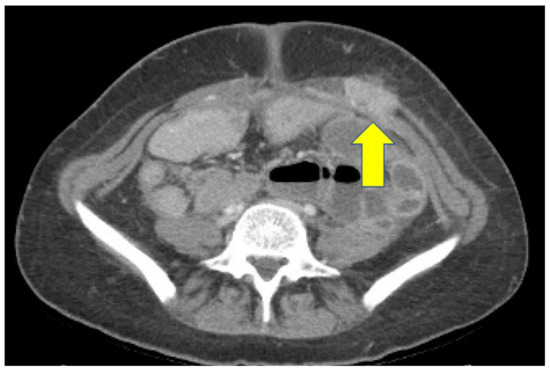

2. Case Report

2.1. Clinical Course